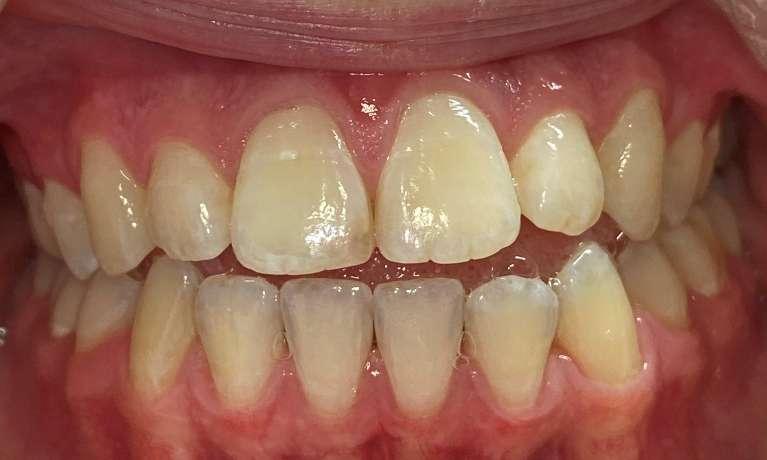

She came to us with a deep bite due to her lower front teeth sitting too high and her two front teeth pushed forward. Using Invisalign, we moved her lower front teeth down into their proper position and pulled the two front teeth back into place. She also needed a deep cleaning to removed deep buildup and restore her gum health. The results are beautiful and healthy!